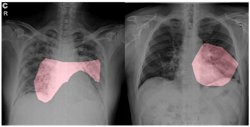

For qualitative analysis, the team explored how COVID-Net makes predictions by leveraging GSInquire—a proprietary technique from DarwinAI that provides insights into how deep neural networks reach decisions. Figure 6 shows critical factors identified in sample COVID-19 chest radiography images. COVID-Net identifies localized areas within the lungs and the chest radiography images as being critical factors in determining whether a radiography image shows a patient with a SARS-CoV-2 viral infection, as shown in red in Figure 6. The ability to interpret and obtain insights into how the proposed COVID-Net detects COVID-19 infections is important for three reasons: